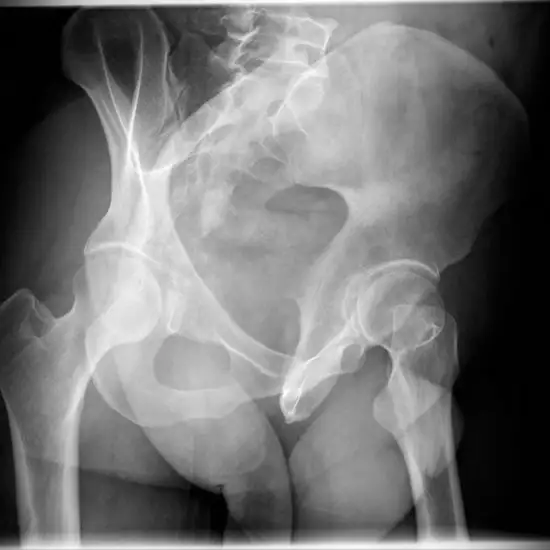

X-ray SI Joint Oblique View

An X-Ray SI Joint Oblique View is a test to see the back region where the spine and pelvis meet (hip bones).

The doctor prescribes this test to identify and diagnose the cause of lower back discomfort, which might be sacroiliitis (inflammation of this joint) or ankylosing spondylitis (a form of arthritis that affects the spine).